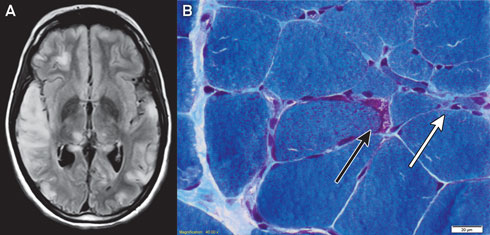

Magnetic resonance imaging of the patient’s brain demonstrated increased T2 signal involving grey and white matter throughout both cerebral hemispheres, most confluent in the right temporal and parietal lobes (Box 1, A). An electroencephalogram displayed a slow rhythm with epileptic activity in the temporal and centroparietal regions.

Histological examination of a biopsy of the gastrocnemius muscle was consistent with MELAS syndrome (Box 1, B). Electron microscopy of a muscle biopsy sample revealed mitochondria with abnormally arranged cristae and abnormal electron densities. Mitochondrial respiratory chain enzyme studies on muscle samples were within normal limits, but the common m.3243A>G mutation in the MTTL1 gene was detected in about 70% of the mitochondrial DNA (mtDNA) in muscle tissue and in 10% of the mtDNA of the peripheral blood.